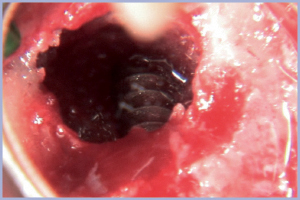

Iniziamo l’osteotomia sotto irrigazione del sito implantare 1.4 (figg. 8, 9) e inseriamo un impianto Exacone® diametro 3,3 (figg. 10-12). Passiamo alla zona distale di grande rialzo con l’esecuzione dell’antrostomia (visione vestibolare e mesiale, figg. 13, 14). Dopo aver aperto lo sportello scolliamo e mobilizziamo la membrana di Schneider (fig. 15). Procediamo all’osteotomia dei siti implantari 1.5 e 1.6 (figg. 16, 17) e inseriamo due impianti Exacone® diametro 3,3 in sede 1.5 e 1.6 (figg. 18, 19). L’inserimento dei due impianti in sede 1.5 e 1.6 spinge e solleva la membrana di Schneider (fig. 20), creando uno spazio da riempire con biomateriale dopo accurato lavaggio con antibiotico (figg. 21-23). Proteggiamo con una membrana in collagene riassorbibile la cavità di accesso all’antro del seno (fig. 24). L’intervento si completa con una sutura attenta che possa garantire la chiusura stabile del campo operatorio (fig. 25).

- Fig. 15